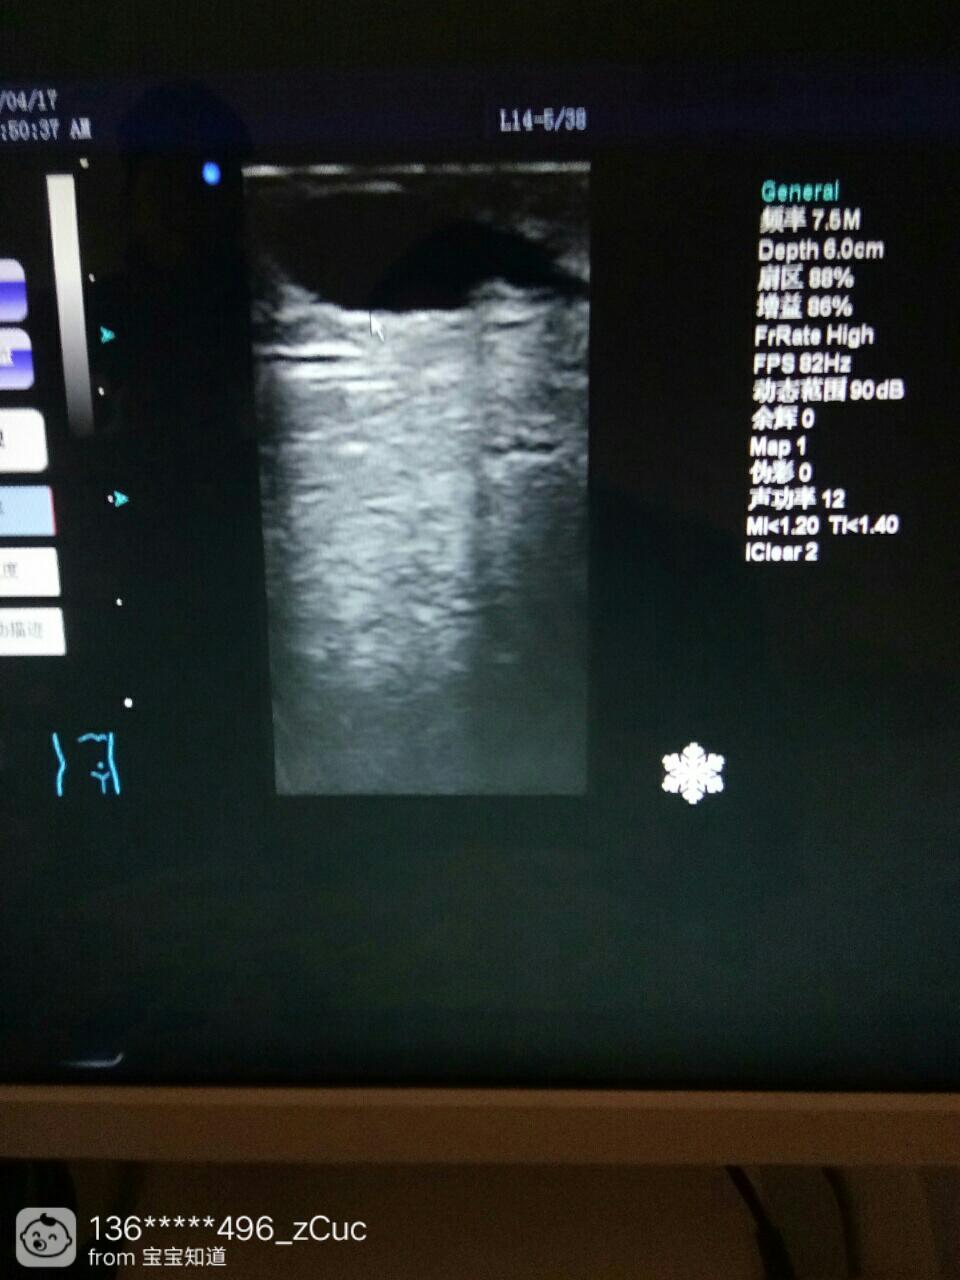

剖腹产,刀口处有个囊肿

剖腹产现急抹在三月零三天了,刚满月的时候去做B超,说刀口处有个囊肿,说不碍事,医生说让过了100天再去看看,有没有吸收了,吸收了就好了,没吸收就得开呈则刀取出了,昨天晚上肚子刀口处突然不敢动了,摁崭垃生一摁就很痛,翻身压着都好痛,怎么回事,哪个姐妹懂一点,麻烦指点一下